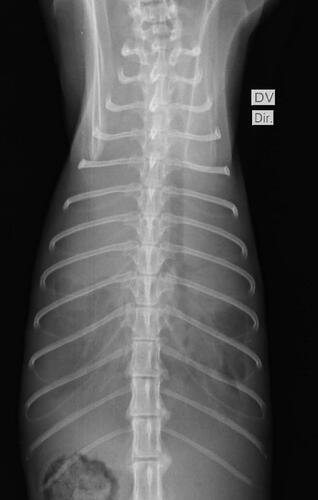

Essa vaquinha é para custear o tratamento do nosso pequeno Loki. Ele é um gatinho lindo que gosta de carinho (quando ele quer) e que ama subir em tudo que pode. Notamos que o Loki estava emagrecendo, e no dia 22-06 ele acordou muito ofegante, com isso levamos para o hospital veterinário saude animal aqui em Maringá-PR. Lá foi constatado que havia líquido no pulmão, e por isso ele estava sem conseguir respirar. Foi feito todo o tratamento para retirada do líquido, analises e exames. Essa primeira parte conseguimos pagar com os limites dos cartões que temos, mas infelizmente chegou a notícia que temiamos.

Loki foi diagnosticado com FELV e devido a essa doença um linfoma apareceu em seu pulmão, hoje Loki está medicado e melhor, mas para que possa sobreviver será necessário uma série de quimioterapias, aproximadamente 4 meses de tratamento. O valor da quimio que deve ser feita semanalmente é R$ 300,00 reais, além disso ele deve realizar exames de Raio X a cada 15 dias e hemogramas para acompanhar a diminuição do tumor. Incluindo os custos com medicação precisamos do valor de R$ 6 mil reais para o tratamento completo, para que o Loki tenha uma chance de viver mais alguns anos. Contamos com a ajuda de todos vocês nessa luta, o Loki é parte da nossa família, e não conseguimos imaginar a nossa vida sem ele.